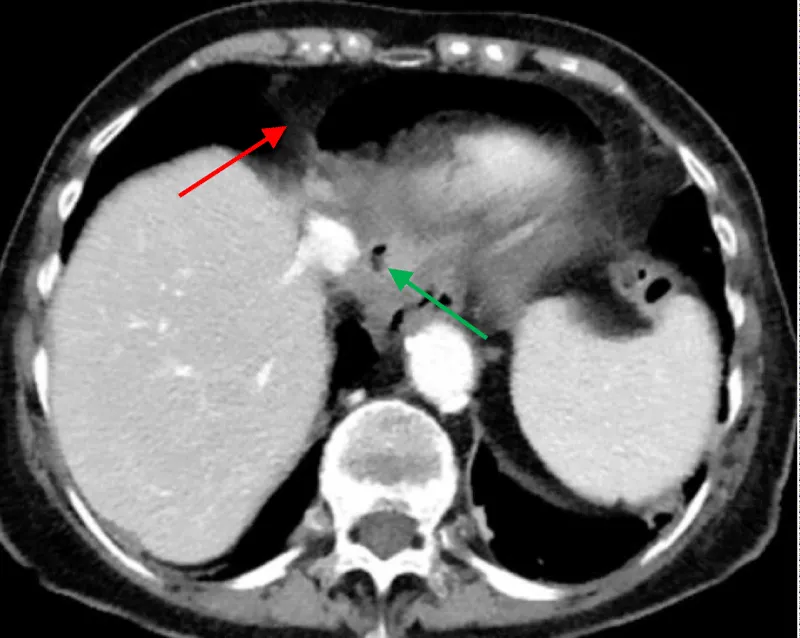

The approval of the hospital’s ethics committee was obtained to present the following case. A 78-year-old female patient was admitted to our hospital with complaints of recurring epigastric pain and diarrhea. The clinical workup revealed collagenous colitis. Upper GI endoscopy was normal. Her medical history included gastroesophageal reflux treated by Nissen fundoplication in 1980 with redo surgery in 2010. While hospitalized, she presented acute retrosternal and epigastric pain not responding to usual medication. Clinical evaluation revealed hemodynamic stability, pericardial metallic tinkling friction rub, mill wheel murmur, and no signs of peritonism. Blood analysis showed a slight inflammation while high-sensitive troponin dosage and leukocytosis were within normal range. Radiologic evaluation by CT scan revealed pneumopericardium associated with a fistula path going from the Nissen’s fundoplication valve towards the pericardial cavity (Figures 1,2).

Figure 2: CT scan showing pneumopericardium (red arrow) and pathologically edematous Nissen’s valve (green arrow).